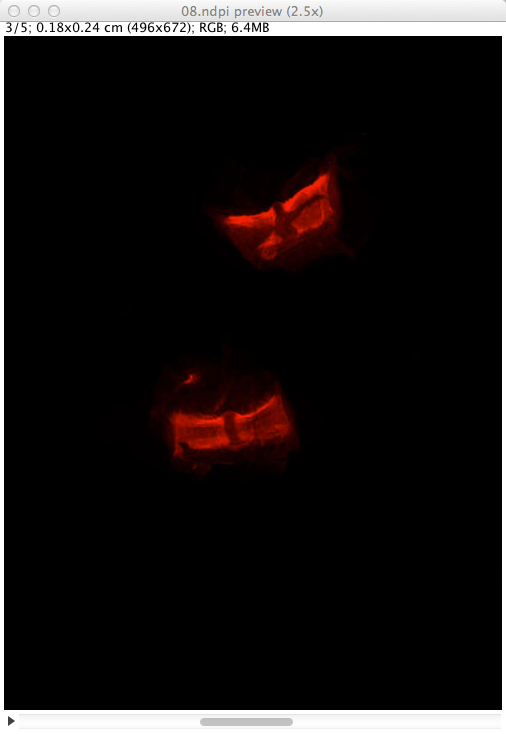

Figure 3 - Preview image of a NDPI file with several focalization levels in ImageJ.

The NDPI file 08.ndpi contains images at 5 different focalization levels. Therefore, its preview image is displayed as a stack of 5 images.